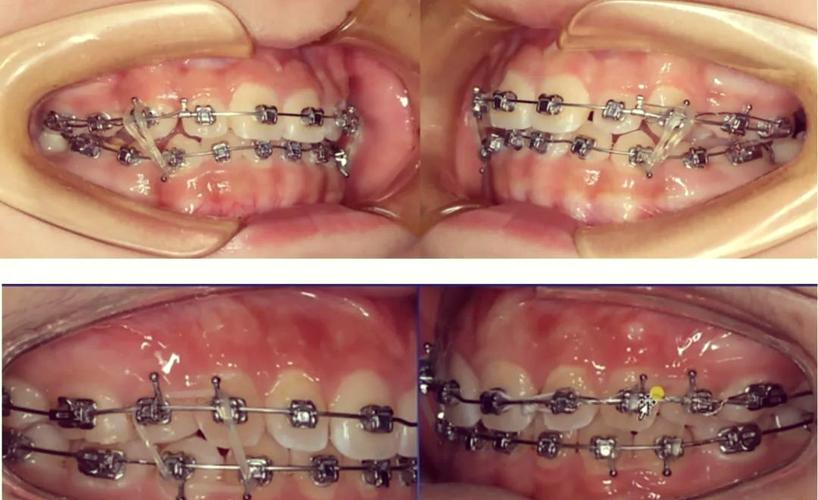

传统固定矫治器是牙齿牵引的经典方法,通过将托槽粘接在牙齿表面,配合弓丝、结扎丝、牵引钩等附件,施加力量移动牙齿,常见类型包括方丝弓矫治器、直丝弓矫治器等,适用于各类错颌畸形,如牙列拥挤、深覆合、深覆盖、反颌等。

- 托槽粘接:使用树脂将金属或陶瓷托槽精确粘接在牙齿唇颊面或舌腭面,托槽槽沟为弓丝提供施力轨道。

- 弓丝弯制与安装:根据牙齿移动需求,将不锈钢丝或镍钛弯制成特定形态(如平直弓、摇椅弓),通过结扎丝或橡皮圈固定于托槽槽沟内,利用弓丝的弹性回缩力牵引牙齿。

- 牵引装置附加:在托槽或磨牙带环上焊接牵引钩,通过橡皮链、螺旋弹簧或弹力线连接需要移动的牙齿与支抗牙,实现“拉”或“推”的效果(如关闭间隙、内收前牙)。

- 定期调整加力:每4-6周复诊一次,更换牵引橡皮链、调整弓丝形态或更换更粗的弓丝,维持牵引力的持续作用。